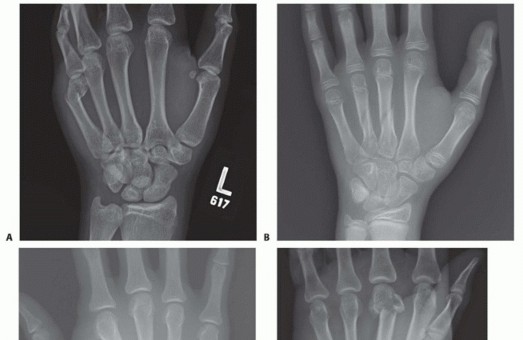

Once reduced, fixation can be achieved via crossed Kirschner wires or retrograde intramedullary pinning (the "bouquet" technique). However, the modern gold standard for minimally invasive fixation is the retrograde intramedullary headless compression screw. A small stab incision is made over the dorsal aspect of the flexed MCP joint. The entry portal is meticulously established in the articular "safe zone" of the metacarpal head—specifically the dorsal-ulnar or dorsal-radial collateral recess, strictly avoiding the central weight-bearing articular cartilage.

A guidewire is advanced down the medullary canal across the fracture site under fluoroscopic guidance. After confirming perfect rotational alignment and length, the canal is sequentially broached or drilled, and an appropriately sized headless compression screw is buried beneath the articular cartilage. This technique provides robust, load-sharing stability that allows for immediate, unrestricted active range of motion, vastly reducing the incidence of postoperative stiffness compared to traditional K-wire constructs.

Clinical & Radiographic Imaging Archive